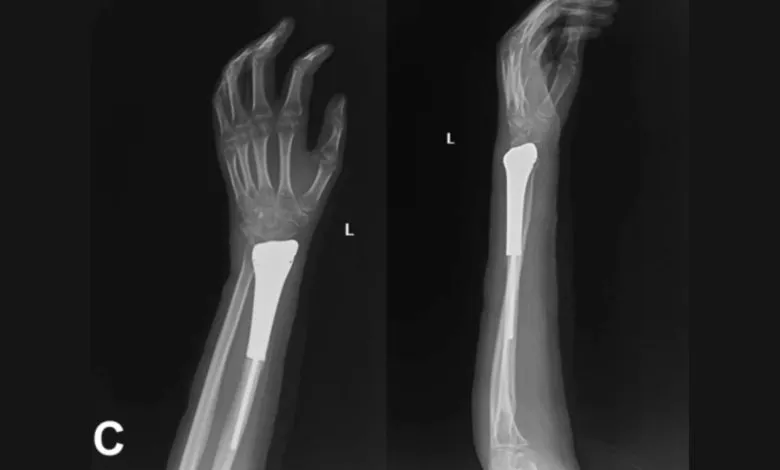

中国一家医院的研究人员开发了一种结合了3D打印全金属假体与网状补片的手术技术,用于治疗桡骨远端骨巨细胞瘤。

这些假体是定制化的骨水泥3D打印、完全集成的金属假体,旨在增强整个治疗和恢复过程中的稳定性。

团队报告称,患侧的平均握力为健侧的64.2%,同时也评估了关节活动度的数值。

术后未发生假体置换后的无菌性松动、腕关节半脱位或感染,也未观察到肿瘤复发或转移。

其中一例在术后12个月出现了尺骨撞击综合征,伴有尺骨正向变异和月骨退行性改变。